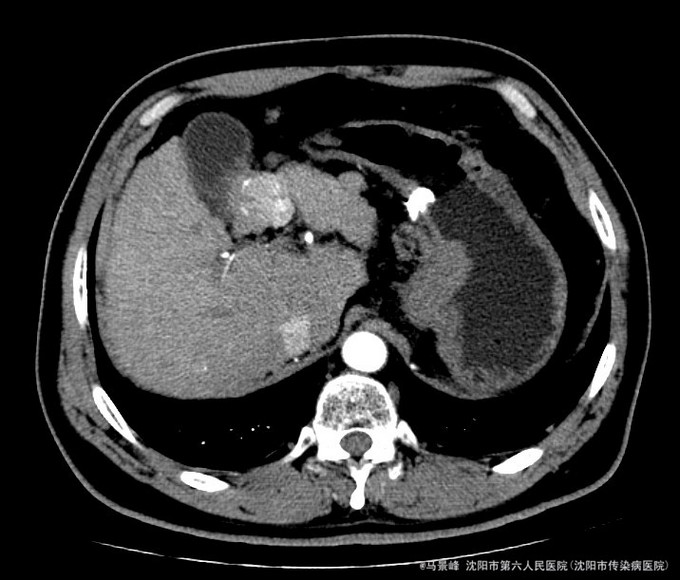

查体:巩膜无黄染,心肺听诊无异常,腹软,无压痛,肝脾肋下未触及,移动性浊音阴性,双下肢无浮肿。 入院后化验结果:丙氨酸氨基转移酶 24 U/L、天门冬氨酸氨基转移酶 36 U/L、碱性磷酸酶 101 U/L、γ-谷氨酰转肽酶 96 U/L、胆碱酯酶 6127 U/L、总蛋白 80.8 g/L、白蛋白 41.4 g/L、总胆红素 30.0 umol/L、结合胆红素 0.0 umol/L、非结合胆红素 16.5 umol/L、δ胆红素 13.5 umol/L。葡萄糖 7.77 mmol/L。乙型肝炎病毒表面抗原 阳性(+) 、乙型肝炎病毒核心抗体 阳性(+) 。甲胎蛋白 3.49 ng/mL。 CT检查示:肝脏形态不规整,肝裂增宽,肝尾叶体积相对增大,各叶大小比例失调,肝实质密度不均,肝内可见多个大小不等结节影,较大者位于肝Ⅳ段胆囊旁,其边缘可见条状碘油沉积,大小约3.3x3.05cm,增强扫描动脉期其边缘轻度强化,门脉期及延迟期扫描呈稍低密度,病灶内坏死区未见强化,其余结节无明显强化,较大者位于Ⅷ段,约1.2cm大小,延迟期呈稍低密度,门脉主干及左右支纤细,左支充盈欠佳,脾脏缺如,胆囊不大,壁增厚,其内密度均匀,胰头区可见一囊性密度影,大小约2.11cm,增强扫描无强化。肝内外胆管未见明显扩张,食管下段胃底贲门区见扩张扭曲的血管影,腹膜后未见明显肿大淋巴结。 患者CT所见胆囊旁病灶碘油流失,且动脉期仍有强化,提示肿瘤仍有血供。

诊断:1、乙肝肝硬化 失代偿期;2、原发性肝癌TACE术后 治疗:入院后除加强休息、抗病毒治疗外,行增强CT检查,发现肝癌TACE治疗后胆囊旁病灶碘油流失,且动脉期仍有强化,提示肿瘤仍有血供。遂于局麻下再次行TACE治疗。